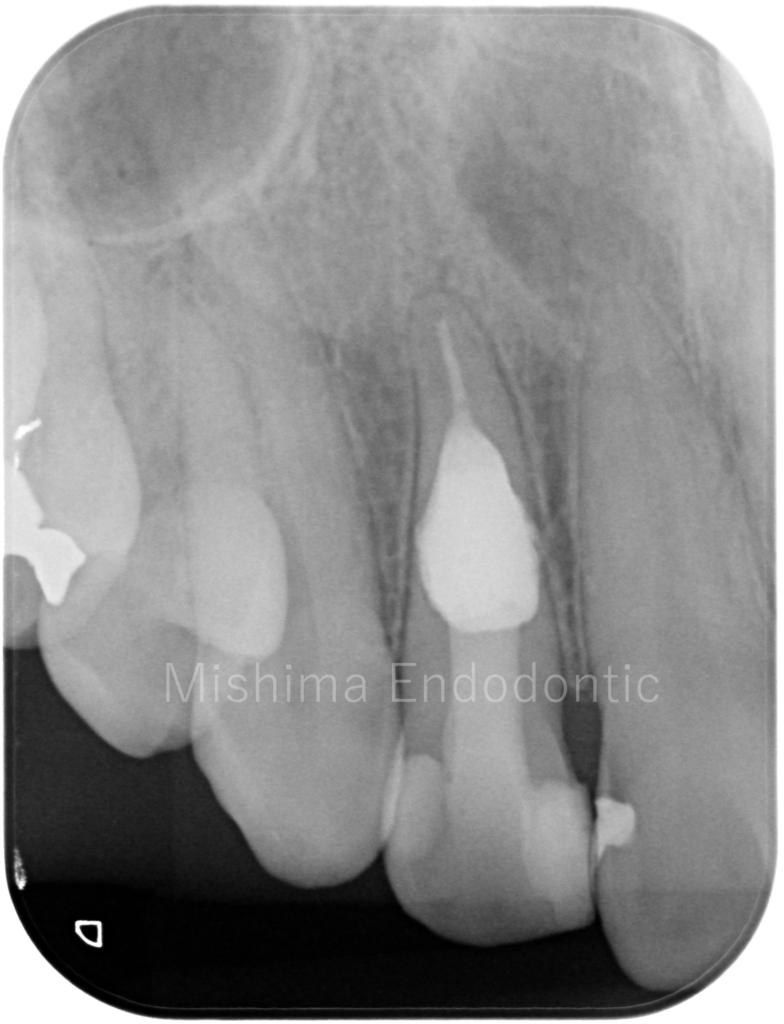

After

| 治療内容 | 歯髄診査により生活反応は認めない。X線にて内部炎症性吸収と診断。根管内を精査したところ、吸収部より根尖の歯髄は生活していた。根管治療を行い、バイオセラミックのパテにて充填。術後、症状、以上所見は認めず経過は良好。 |

術直後

術後3カ月